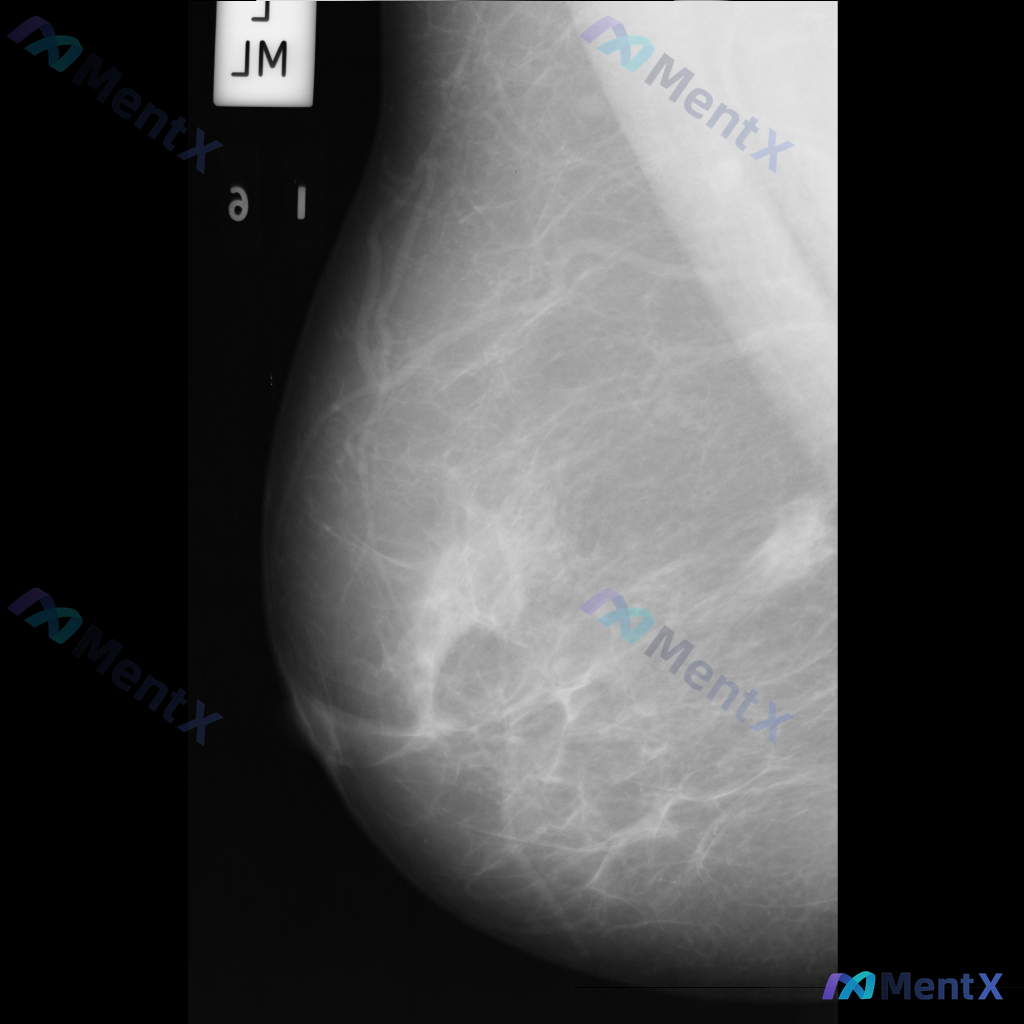

各位同道好,今天分享一则左乳钼靶病例,影像表现如下: 1. 左乳下方(近乳头区)可见一个边界清晰、形态卵圆形的等/稍高密度肿块影; 2. 左乳中央及下象限腺体局部密度增高和结构紊乱; 3. 散在分布的粗大点状钙化。 上传的钼靶影像编号为mdb083.png,供大家参考。 针对这组表现,你更倾向于哪种...

整理到一张乳腺钼靶影像的讨论资料,先把关键信息列出来,大家帮忙看看: - 影像类型:左乳内外斜位(MLO位)钼靶 - 背景:乳腺呈多量腺体型(致密型),腺体组织丰富 - 主要发现:左乳下象限可见局灶性不对称密度,伴有腺体结构轻度紊乱 - 其他:目前未见明确的异常钙化、导管增粗或皮肤异常 单看这张影像...